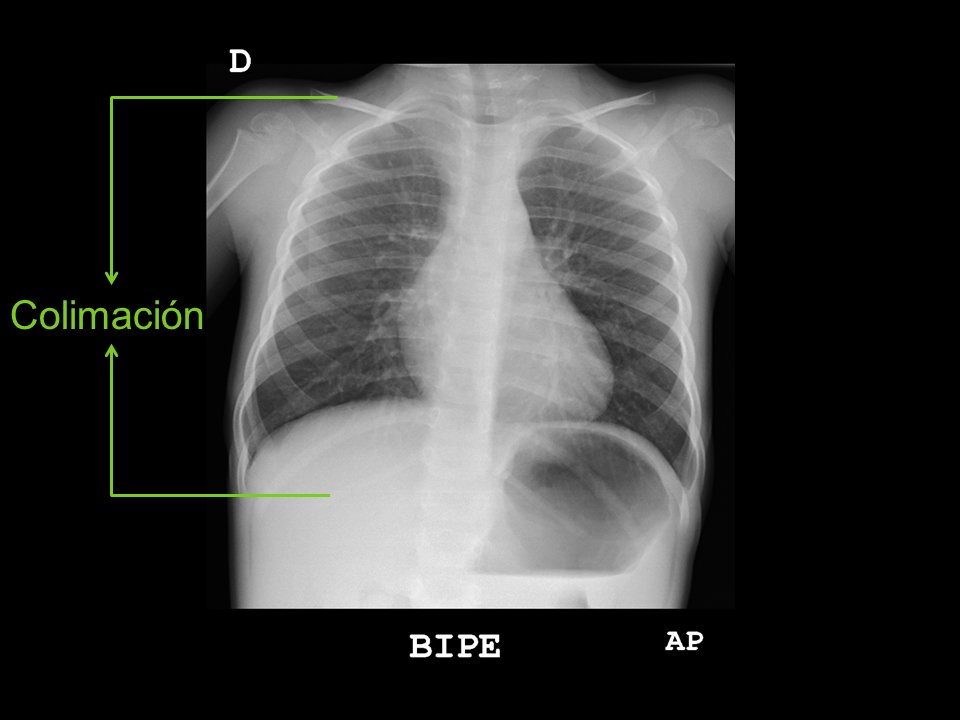

• Colimación: debe incluir las regiones supraclaviculares y la totalidad del diafragma.